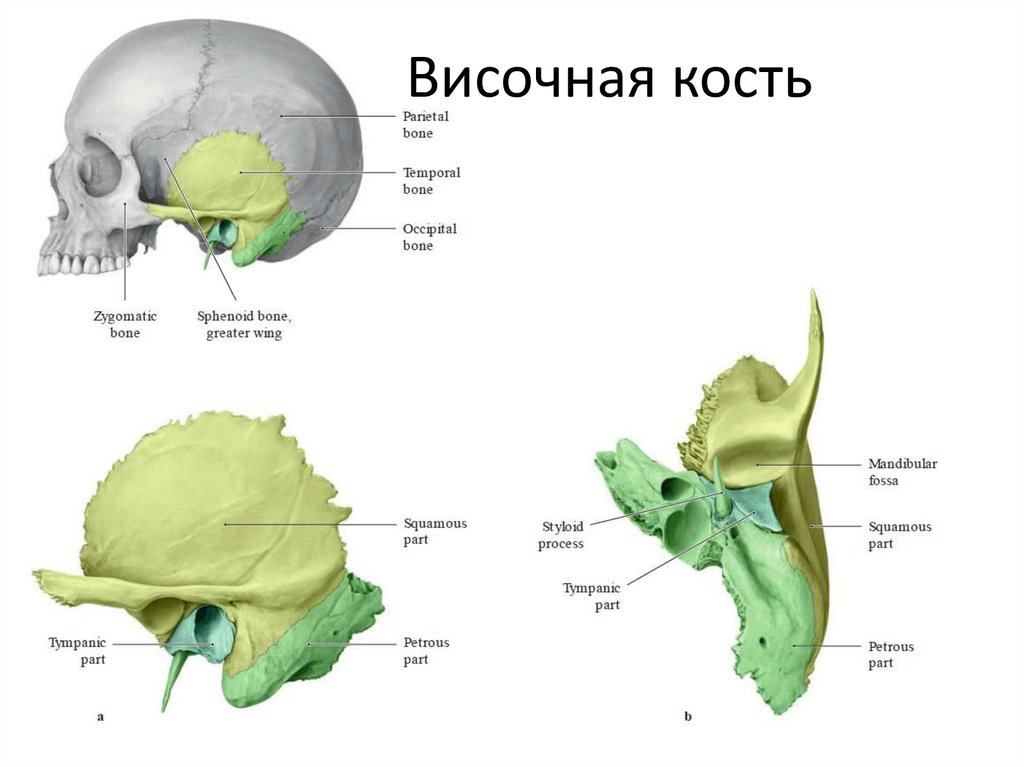

Анатомия и особенности фиссуры петротимпаника